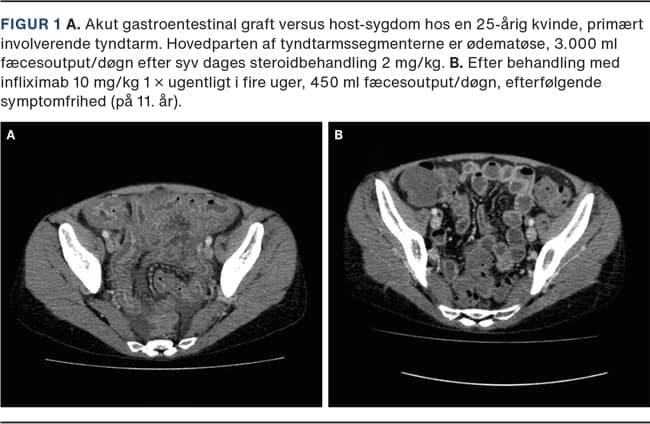

Akut GVHD opstår inden for de første tre måneder efter transplantationen, og oftest er huden involveret, dernæst gastrointestinalkanalen og leveren. På huden udvikles et makulopapuløst eksantem, der i alvorlige tilfælde kan gå over i toksisk epidermal nekrolyse [15]. Gastrointestinalkanalen kan blive svært påvirket med destruktion af epitel, hvilket kan føre til svære diarréer samt væske- og elektrolyttab (Figur 1). Akut GVHD behandles initialt med højdosissteroid, ved terapisvigt tillægges infliximab [16], ruxolitinib [17] eller ekstrakorporal fotoferese [18]. Akut GVHD medfører øget morbiditet og mortalitet i form af infektioner, medicinbivirkninger og organsvigt. Mismatchet donor, høj alder og intensiv konditionering bidrager til øget forekomst af GVHD, men også det fækale mikrobiom er indgået i kliniske studier gennem de seneste år [19]. Der er fundet en sammenhæng mellem et dysbiotisk fækalt mikrobiom med nedsat diversitet, antal genomer og incidensen af akut GVHD. Den kausale sammenhæng er dog ikke påvist endnu, men er et hastigt ekspanderende forskningsområde [20].